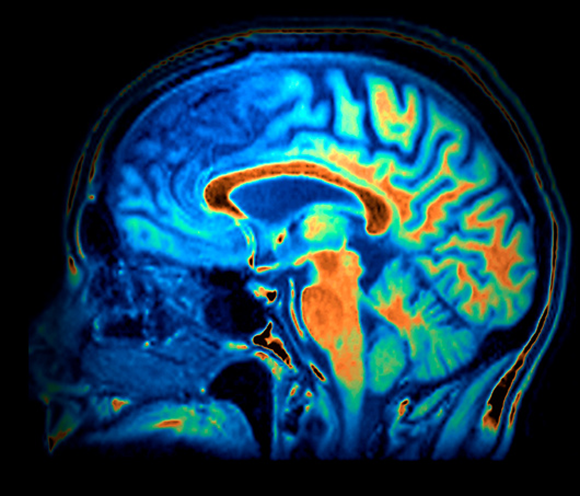

המחלה גורמת להתנוונות של תאי העצב באונה הצידית ובאונה הקדמית של המוח. סריקת MRI של חולה בדמנציה פרונטו-טמפורלית | Zephyr / Science Photo Library